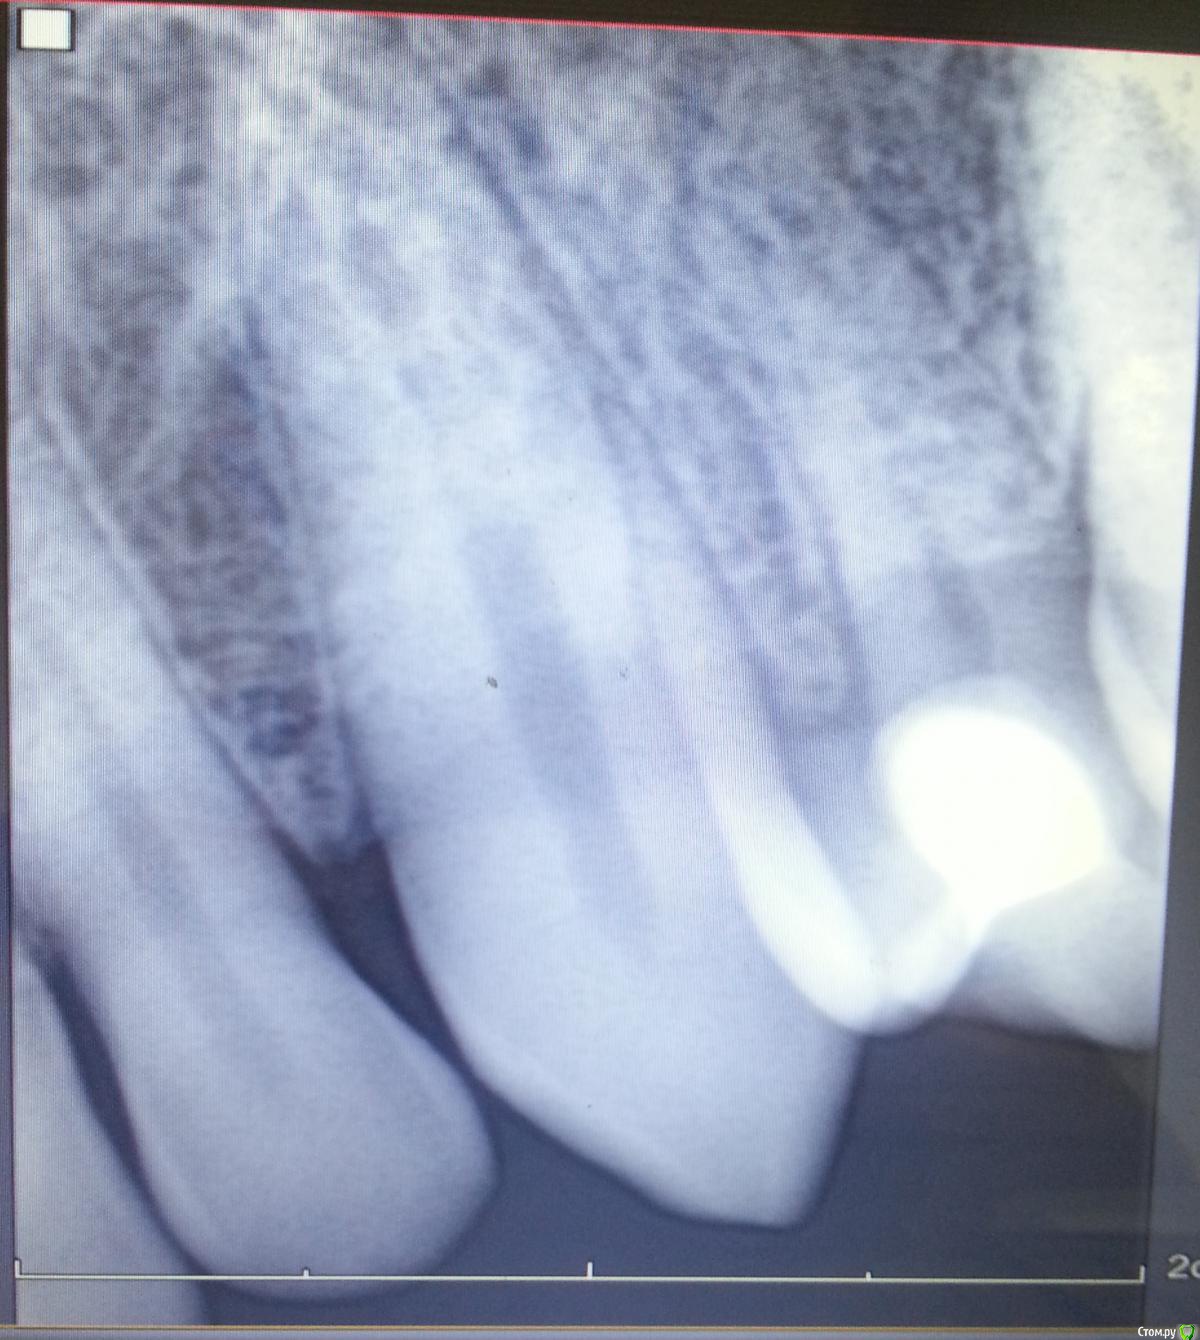

Nitrino1 Опубликовано 17 августа, 2015 Поделиться Опубликовано 17 августа, 2015 (изменено) Здравствуйте коллеги. Обратился пац. Субъективно: боли при давлении на этот зуб. Постоянных болей, спонтанных болей нет.Объективно: отсутствует 24й зуб (аномалия). После 23го сразу 25й. Небольшое покраснение маргинальной десны. Перкуссия 25го болезненна. Холодовой тест отрицательный. Судя по рг там должна быть пломба но внешне как то не определил. Плюс непонятное наложение на клык. Помогите разобраться. Есть мнение что это резорбированная 4ка. Изменено 17 августа, 2015 пользователем Nitrino1 Ссылка на комментарий

Хью Крейн Опубликовано 17 августа, 2015 Поделиться Опубликовано 17 августа, 2015 На рентгене премоляр развернут по диагонали.Пломба -участок интенсивного окрашивания.А уплотнение на корне- скорее всего гранулема в результате хронического периодонтита. Возможно-гиперцементоз. И никаких тайн там нет.Ну попробуйте изменить ракурс снимка,а уж если очень захотите и пациент не против- на КТ. Ссылка на комментарий

Sergdokrg25 Опубликовано 17 августа, 2015 Поделиться Опубликовано 17 августа, 2015 На ИРЗ есть всегда проекционное искажение и наложение соседних теней - здесь по вопросам сверзу вниз -1. зуб двухканальный с 2мя корнями у верхушки (это обведена одна из них) никакой патологии нет, 2. уровень десны с небной части зуба (проекционно удлинен), 3. эффект наложения двух соседних зубов (Да и в следующий раз делайте хотя бы скрин с экрана компьютера - больше сохраняется качество изображения) 1 Ссылка на комментарий